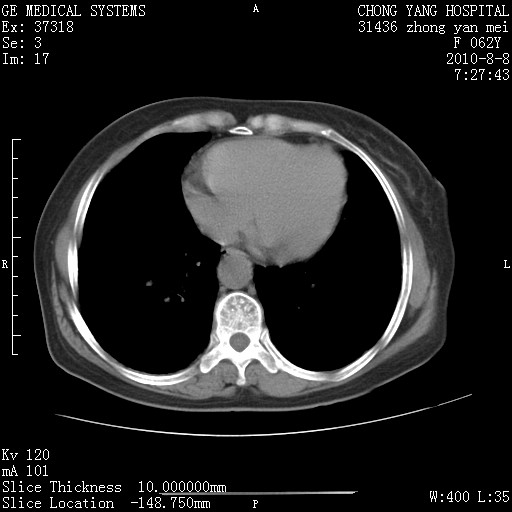

1.肺间质纤维化.

2.纵隔淋巴结肿大。

3.迷走右锁骨下动脉。

两肺间质改变,纵隔淋巴结肿大,需要考虑结节病的可能。